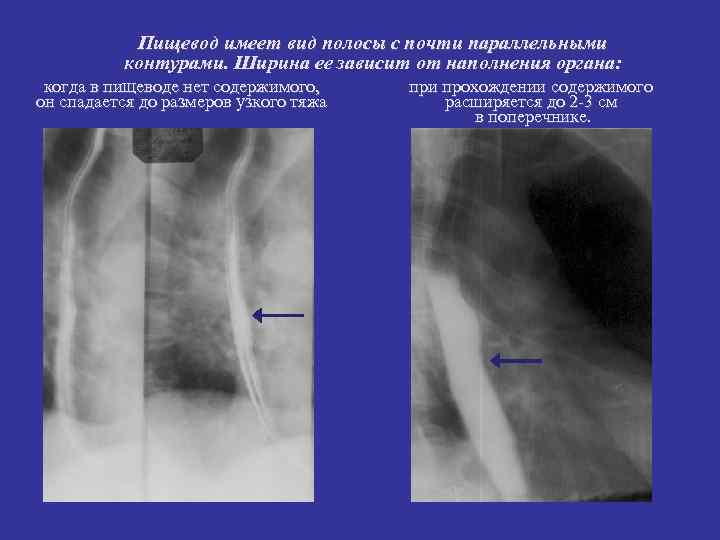

Пищевод имеет вид полосы с почти параллельными контурами. Ширина ее зависит от наполнения органа: когда в пищеводе нет содержимого, при прохождении содержимого он спадается до размеров узкого тяжа расширяется до 2 -3 см в поперечнике.